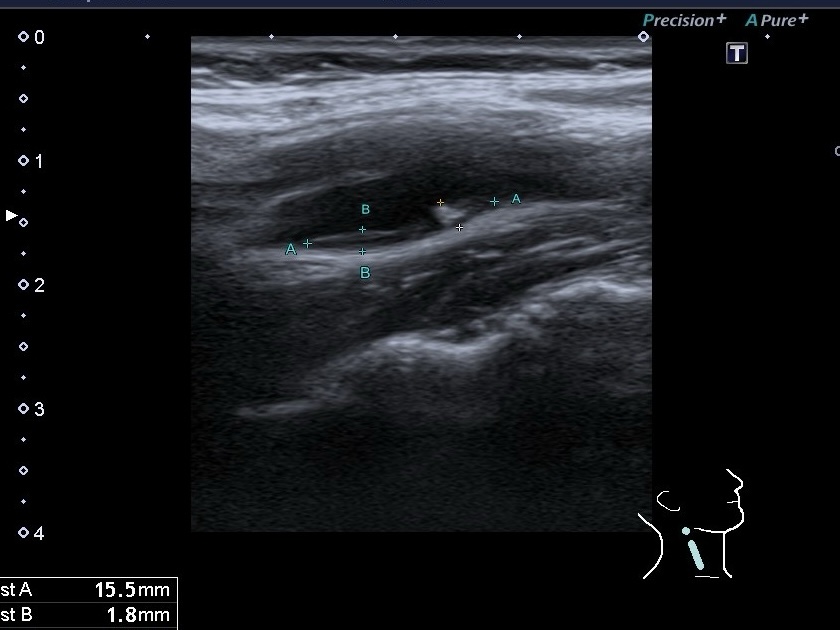

Последнее время при проведении УЗИ сосудов шеи большее внимание уделяется тому чтобы оценить типы атеросклеротических бляшек(АСБ). В зависимости от типа бляшки можно сказать о степени риска возникновения инсульта у пациента. Существует несколько классификаций АСБ. Одна из них Plaque-RADS делит бляшки на 4 категории. Самая опасная АСБ по этой классификации это 4 категория, куда входят бляшки, осложнённые внутренними кровоизлияниями, тромбозами, с повреждённой фиброзной покрышкой. К умеренному риску относятся АСБ 3 типа, которые также делятся на 3 подтипа (а, b, c). К 3а типу относятся АСБ с толстой фиброзной покрышкой, к 3б типу- с тонкой покрышкой. Это при условии, что эту покрышку есть возможность оценить. А вот уже к 3с типу относятся бляшки с изъязвлениями (прерывистой покрышкой)

Разница между 2 и 3 категориями в толщине стенки (максимальная толщина стенки, где бляшка до 3мм-2 тип или больше 3 мм- 3тип).2 категория АСБ считается с низким риском инсультов.

До данной классификации атеросклеротических бляшек существовала долго классификация нестабильности АСБ по эхогенности (Gray-Weale-Geroulakos). Учитывая, что названия классификаций атеросклеротических бляшек многим клиницистам мало известны, мы считаем важным описать характеристики АСБ по её стабильности в первую очередь. К примеру, нестабильная (гомогенная гипоэхогенная) АСБ или нестабильная (гетерогенная, преимущественно гипоэхогенная АСБ) с изъязвлением.